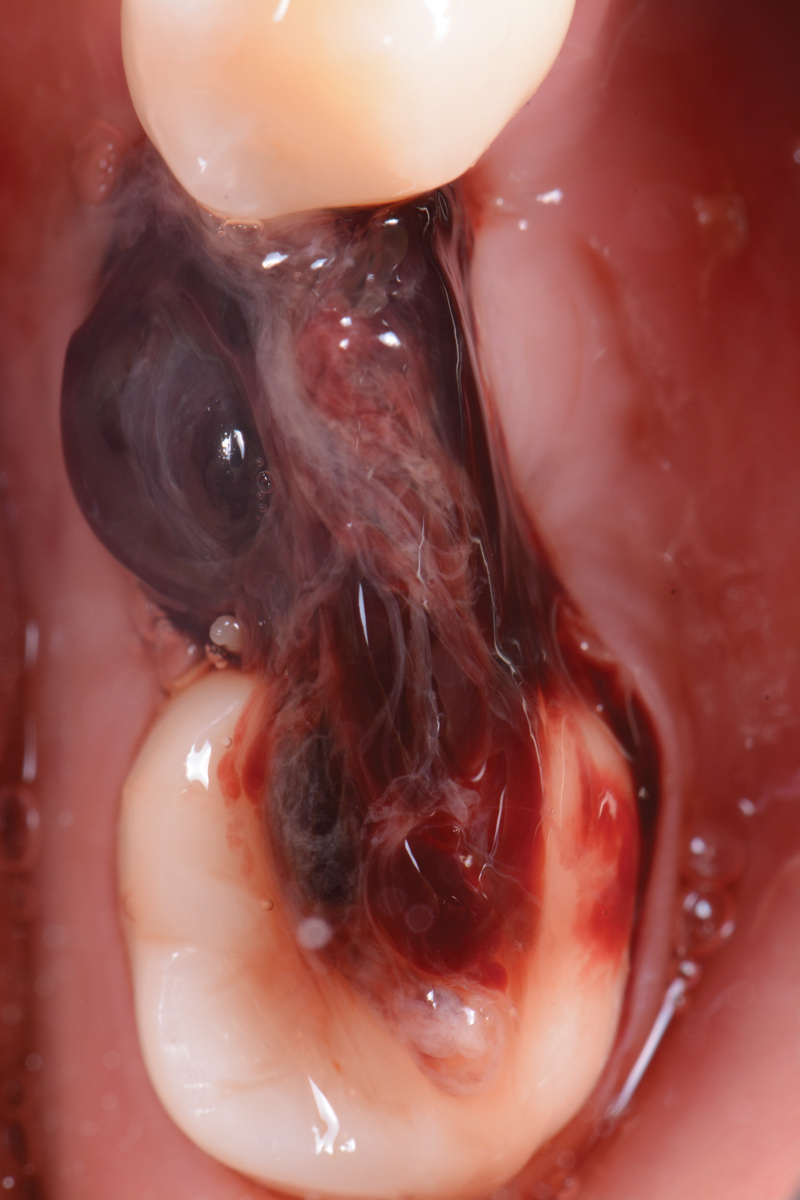

Three months later, the patient was scheduled for second-stage surgery to place a healing abutment. When asked, the patient stated that she had no changes in her medical history. Following local anesthesia infiltration, a crestal incision was made and a full-thickness flap was elevated in the No. 19 area to expose the implant cover screw. A healing abutment measuring 5 mm x 5 mm was placed, and two single interrupted resorbable sutures were used to close the flap.

The following day, the patient presented for an emergency, reporting she began to bleed after she left the office and had continuous bleeding that day and night. Vital signs were normal (blood pressure was 115/65 mmHg, and pulse was 53 beats per minute). The first attempt to control the bleeding included having the patient bite on wet collagen wound dressing and alternate using wet- and dry-gauze compression for 30 minutes. After the removal of the collagen wound dressings, the bleeding restarted spontaneously. The sutures were then removed, and a collagen wound dressing was placed under the flap. Two single interrupted sutures were used, and a third suspended suture was placed around the healing abutment to obtain compression in the area. The patient was observed for 1 hour. During this time, wet-gauze compression was used on the area until the bleeding stopped. The patient was then dismissed and told to reapply gauze with pressure if bleeding recurred (Figure 1 through Figure 5).

Fig 1. Second-stage surgery.

Figure 1

Fig 2. One day postoperative.

Figure 2